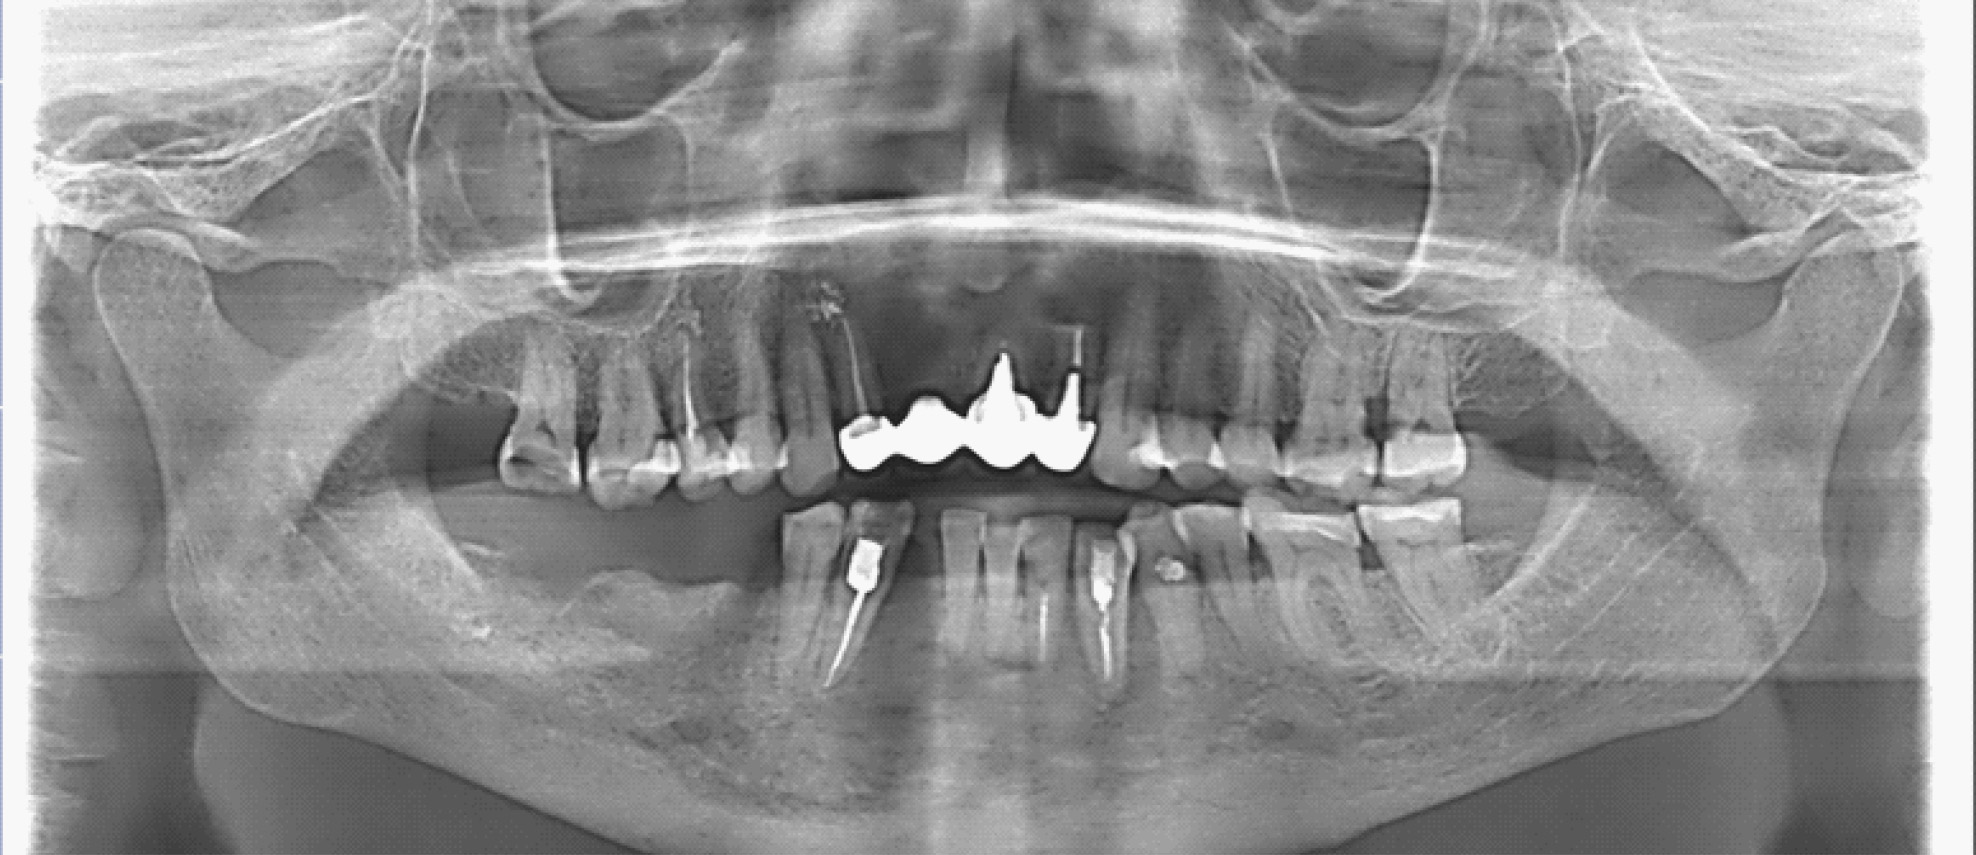

В полости рта: нарушение целостности слизистой оболочки полости рта, субтотальный остеонекроз альвеолярной части нижней челюсти слева. Вид костной тканей серо-коричневого цвета, пальпация безболезненная. На ортопантомограмме отмечается ограниченный участок деструкции костной ткани нижней челюсти с поражением тела нижней челюсти. Одонтогенной причины заболевания нет (рис. 1).

Рис. 1. Клинические проявления бисфосфонатного остеонекроза нижней челюсти во фронтальном отделе

Пальпация безболезненная. На ортопантомограмме определяются лунки зубов 4.7, 4.5 без явных признаков секвестрирования (рис. 3).

Рис. 3. Ортопантомограмма на этапе лечения остеонекроза нижней челюсти справа у пациентки Б. в 2022 г.